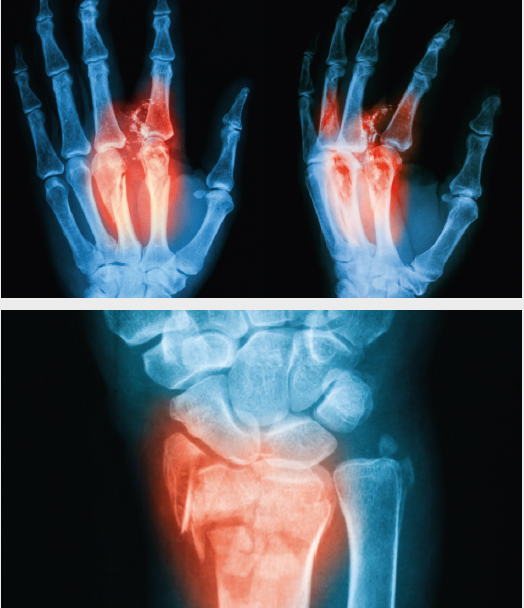

Inflammatory Arthritis such as Rheumatoid and Psoriatic arthritis, as well as osteoarthritis, can damage the multiple joints of the hand and wrist as well as the surrounding structures. They can cause damage to the articular surface of the joint. “Locking” of the joints can occur if fragments of bone break off the elbow and become lodged between the moving parts of the joint, causing reduced movement and pain. Synovitis or inflammation of the lining of the joints is seen with both conditions. Arthroscopic or key-hole surgery can wash out the wrist joint and allow your surgeon to remove loose pieces of bone or cartilage with small instruments. Synovitis of the lining of the wrist joint can be shaved away to give pain relief. Wrist, thumb base and finger joint replacement or fusion is recommended for patients with pain who have failed to respond to other treatments. This choice of treatment is tailored to each individual patient and need detailed discussion with your surgeon.